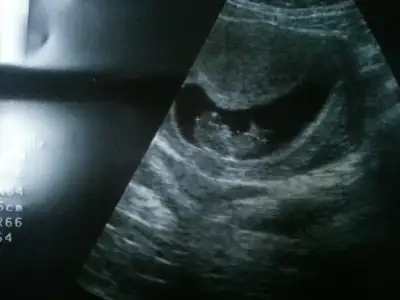

dr soylemeden siz gorun genital nub teorisi ( bebegin cinsiyeti)

Baya bi sayfa kurcaladim burda bi sürü resme baktım bende erkek diye yordum ama objektif olamıyorum :)

doktor yorum yapmadı mı bu fotoya erkek cnmkızlar benimkinede bakarmisiniz :)

çok küççük cnm :)Kızlar benim melegmede bi bakarmısınız anlayamadm ben Eki Görüntüle 1339819 Eki Görüntüle 1339826 Eki Görüntüle 1339826

Kiz bebegim ya bence hacerrrr nerdesin su fotoyu nuba koyarmisn tatlim[/QUOTE]ecan77, post: 38331411, member: 315712"]Merhabalar,daha oncedende koymustum,doktorum bilemedi meraktayim..))) 14+5 gunluk bebisim

Lutfen yorum yaparmisiniz,tesekkurler

13 haftayı bekle cnm bu hafta aynı oluyo bazen nublarBu da bizim findik kurdu varsa yorum yapabilen memnun olurum :)